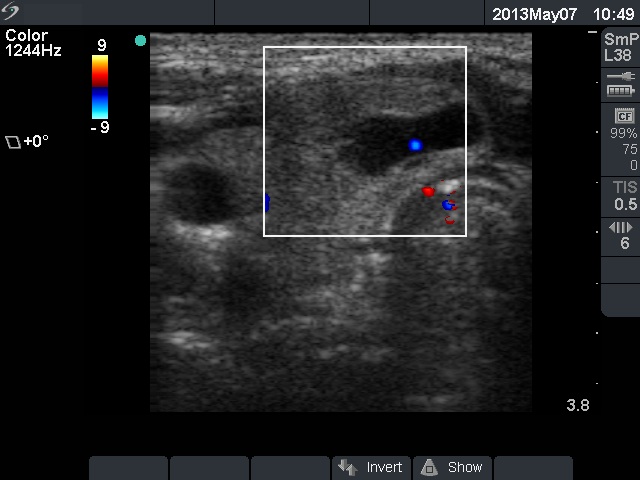

Ethanol sclerotherapy: non-toxic solid nodules - Case 5

Ten years after the therapy (ultrasonographic picture 3)

Right lobe, horizontal scan, color Doppler mode. The vascularization is decreased.